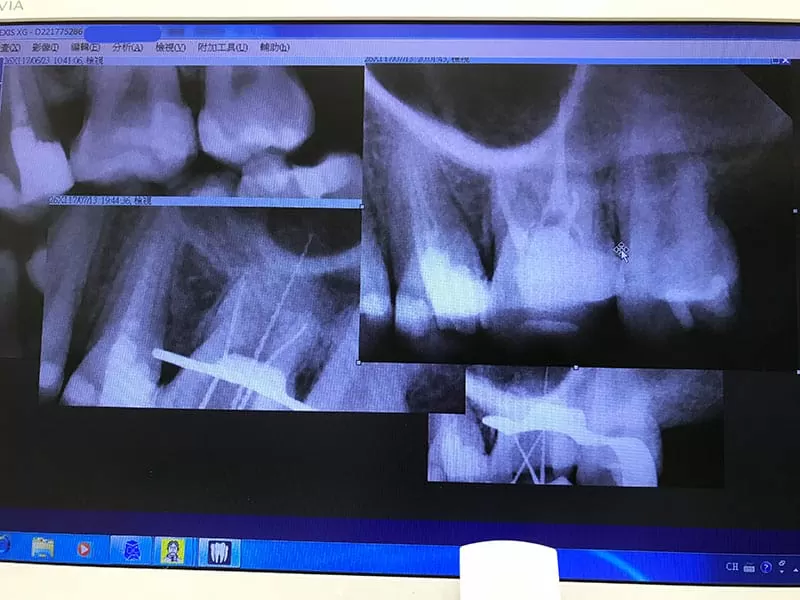

顯微根管治療前,先拍x光片找出病因

施術前詳細的x光

施術處理後 相當乾淨,各個角度都清清楚楚

可以清楚看到完成顯微根管治療的封填狀況,醫師也細心講解了放藥後的狀況,整個顯微根管治療順利結束了! 接下來是轉診牙套部份,整個治療才算圓滿結束~